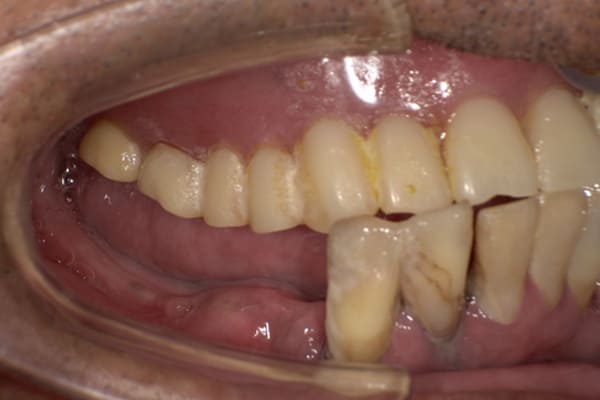

下顎治療前

-

下顎治療後

治療前の入れ歯の奥歯は、治療後の義歯と比較しても分かるように、歯が削れ平らになった状態です。

これにより奥歯のかみ合わせは低くなり、前歯のみが強くあたり、かみ合わせにより上の前歯大きな負担がかかっていたことにより、上の前歯が折れたことが考えられます。